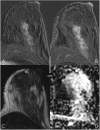

Due to its superior sensitivity, breast MRI (bMRI) has been established as an important additional diagnostic tool in the breast clinic and is used for screening in patients with an elevated risk for breast cancer. Breast MRI, however, is a complex tool, providing multiple images containing several contrasts. Thus, reading bMRI requires a structured approach. A lack of structure will increase the rate of false-positive findings and sacrifice most of the advantages of bMRI as additional work-up will be required. While the BI-RADS (Breast Imaging Reporting And Data System) lexicon is a major step toward standardised and structured reporting, it does not provide a clinical decision rule with which to guide diagnostic decisions. Such a clinical decision rule, however, is provided by the Kaiser score, which combines five independent diagnostic BI-RADS lexicon criteria (margins, SI-time curve type, internal enhancement and presence of oedema) in an intuitive flowchart. The resulting score provides probabilities of malignancy that can be used for evidence-based decision-making in the breast clinic. Notably, considerable benefits have been demonstrated for radiologists with initial and intermediate experience in bMRI. This pictorial essay is a practical guide to the application of the Kaiser score in the interpretation of breast MRI examinations.